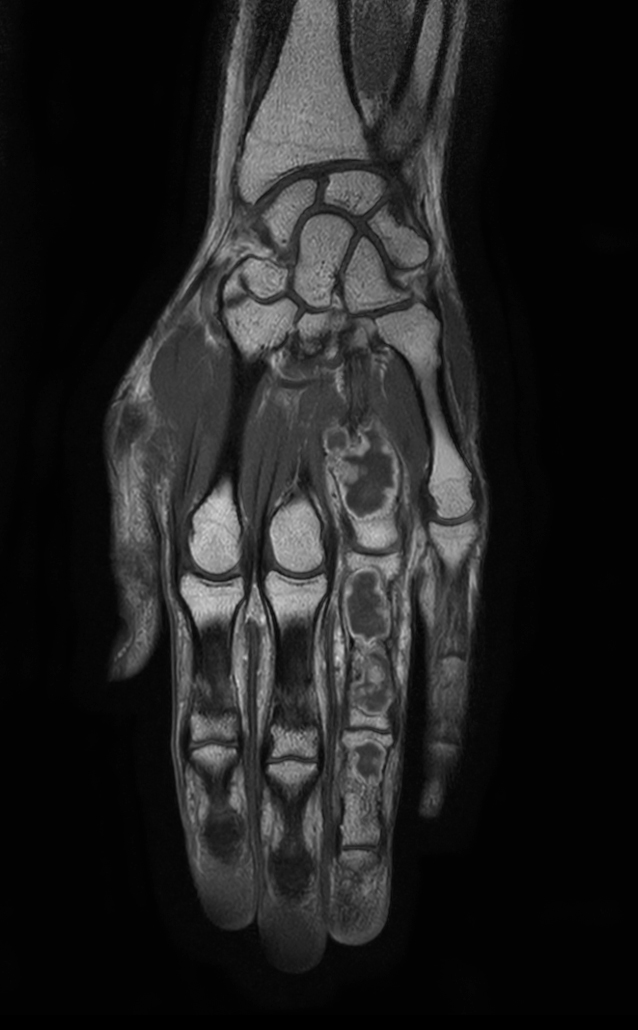

Coronal T1w mDIXON XD TSE (Water only)

Coronal T1w mDIXON XD TSE (In Phase)

Coronal T1w mDIXON XD TSE (Partial FatSat)